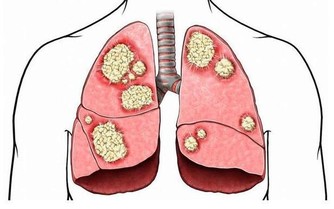

4、肺

生氣易引起吸就會急促,甚至出現過度換氣的現象,肺泡不停擴張,得不到放鬆,沒時間收縮,

也就得不到應有的放鬆和休息,從而危害肺的健康,嚴重時會引發哮喘等病症。